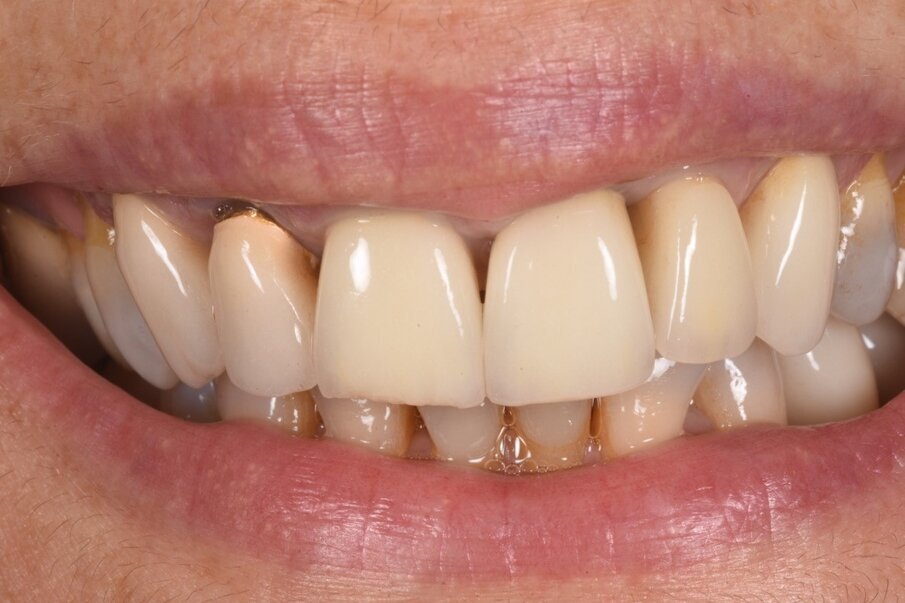

Le radiografie del caso completato nell’inizio del 2010 (Fig. 4) evidenziano la precisione del lavoro che è poi stato mantenuto nel corso degli anni. L’incisivo centrale destro 11 era stato trattato con apicectomia in passato ed era l’unico dente non vitale della riabilitazione. La paziente era seguita dal protesista che aveva portato a termine il caso. Nel 2021 la signora si è ripresentata con sintomatologia sul dente 21. Il lavoro eseguito nel 2010 era ancora in buone condizioni fatta eccezione per 11-12 ove 12 presentava una recessione gengivale con esposizione del collarino della cappetta galvanica che supportava la corona in ceramica e 11 presentava una piccola fistola nella sua porzione vestibolo distale (Figg. 5-7). La diagnosi era abbastanza semplice, l’11 aveva una frattura verticale e una prognosi infausta.